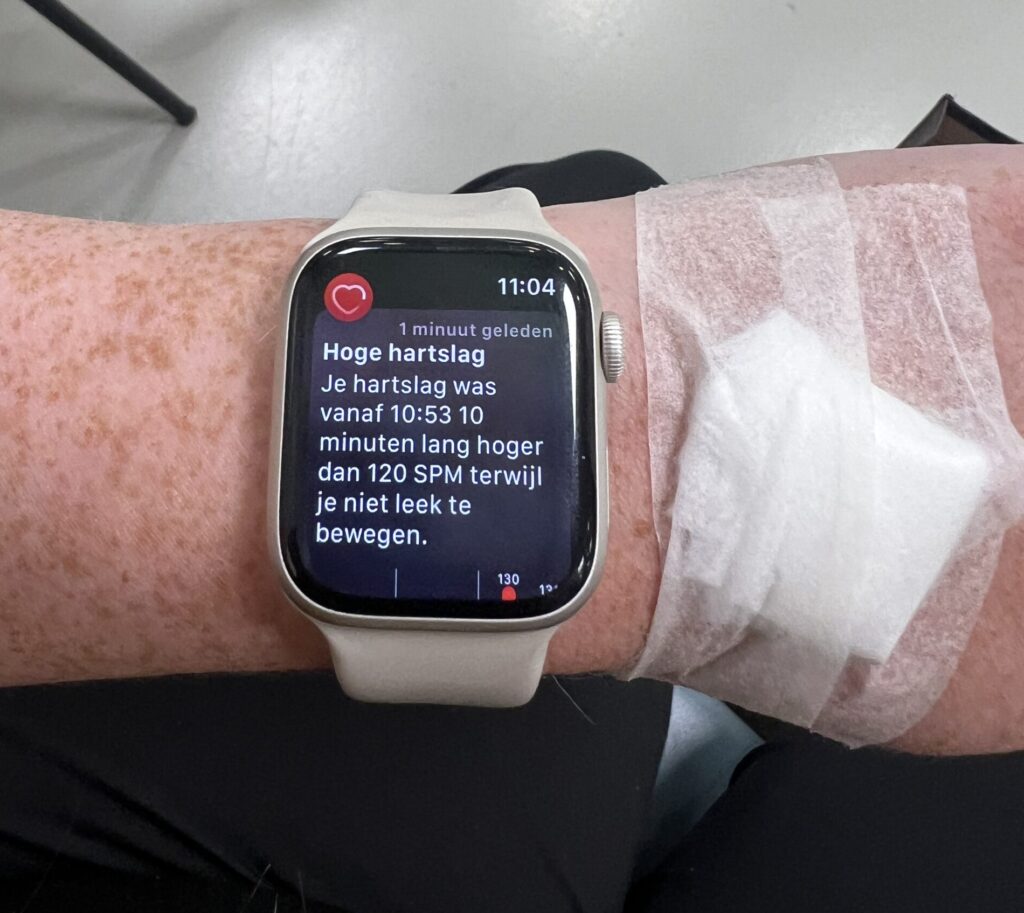

- Hoge bloeddruk

- Pre eclampsie / HELLP syndroom

Op 16 juni meldde ik me om 09.00 uur in het Rijnstate voor de OGTT.Michael had me afgezet. De test

Op 10 juni waren we weer in het ziekenhuis.De afspraak stond om 10.50 uur en Michael ging natuurlijk met me